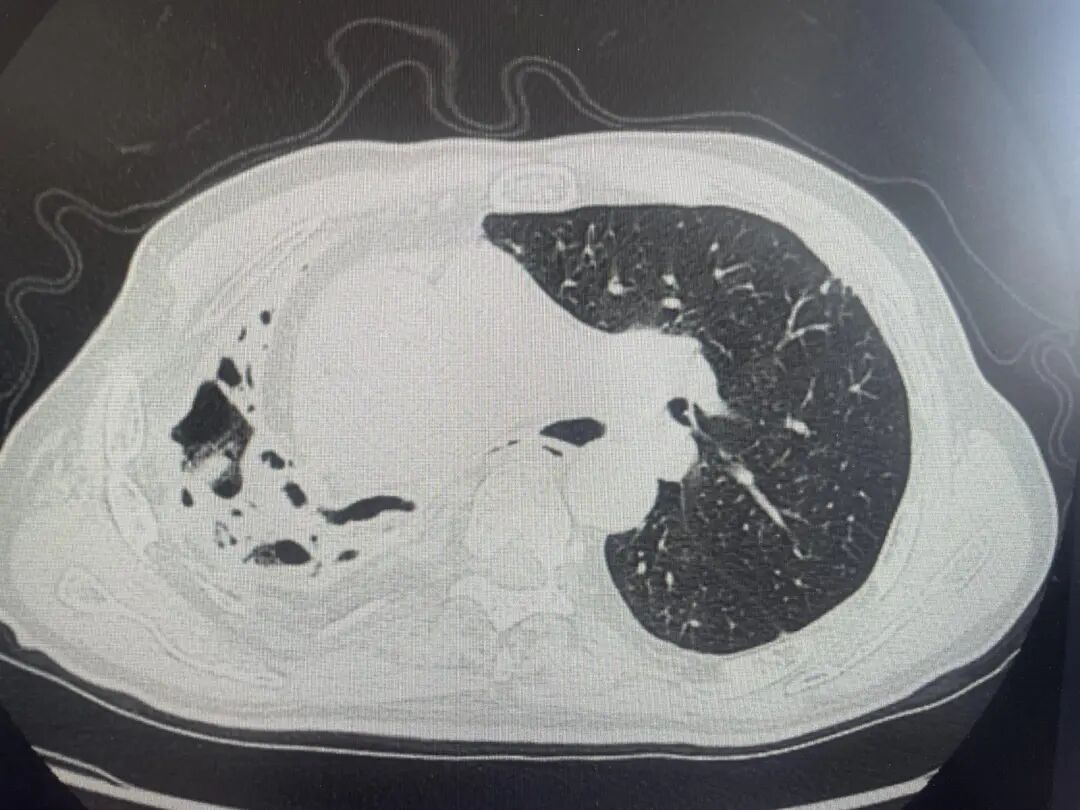

肺部CT结果显示

他的右肺已严重毁损

呈现出典型的蜂窝状改变

肺功能受损严重

▲肺部CT提示王大伯右肺毁损、蜂窝状改变